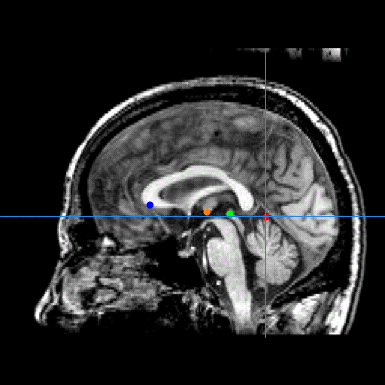

Description: A brain image is aligned to the Talairach standard through a three-step process:

- Mid-sagittal alignment (1) – During the first step, the manual transform editing tool is used to align the brain image mid-sagittal plain with the displayed mid-sagittal markers.

- AC-PC and Origin alignment (2) – During the second step, four anatomical locations are identified -- ventral aspect of the anterior Corpus Callosum (CC), ventral aspect of the Thalamus (TN), Superior Colliculus (SC), and superior aspect of the Cerebellum (CB) -- which are used to align the image to the AC-PC line. Then the origin is identified as the Anterior Commisure.

Screenshots: